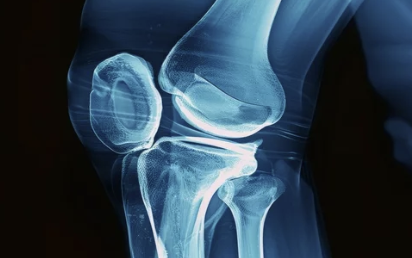

✔ 퇴행성 관절염이 심해지면 무릎 연골이 닳아 뼈끼리 부딪히며 심한 통증 유발

✔ 수술을 통해 손상된 관절을 인공관절로 대체하면 통증 완화 & 활동 가능